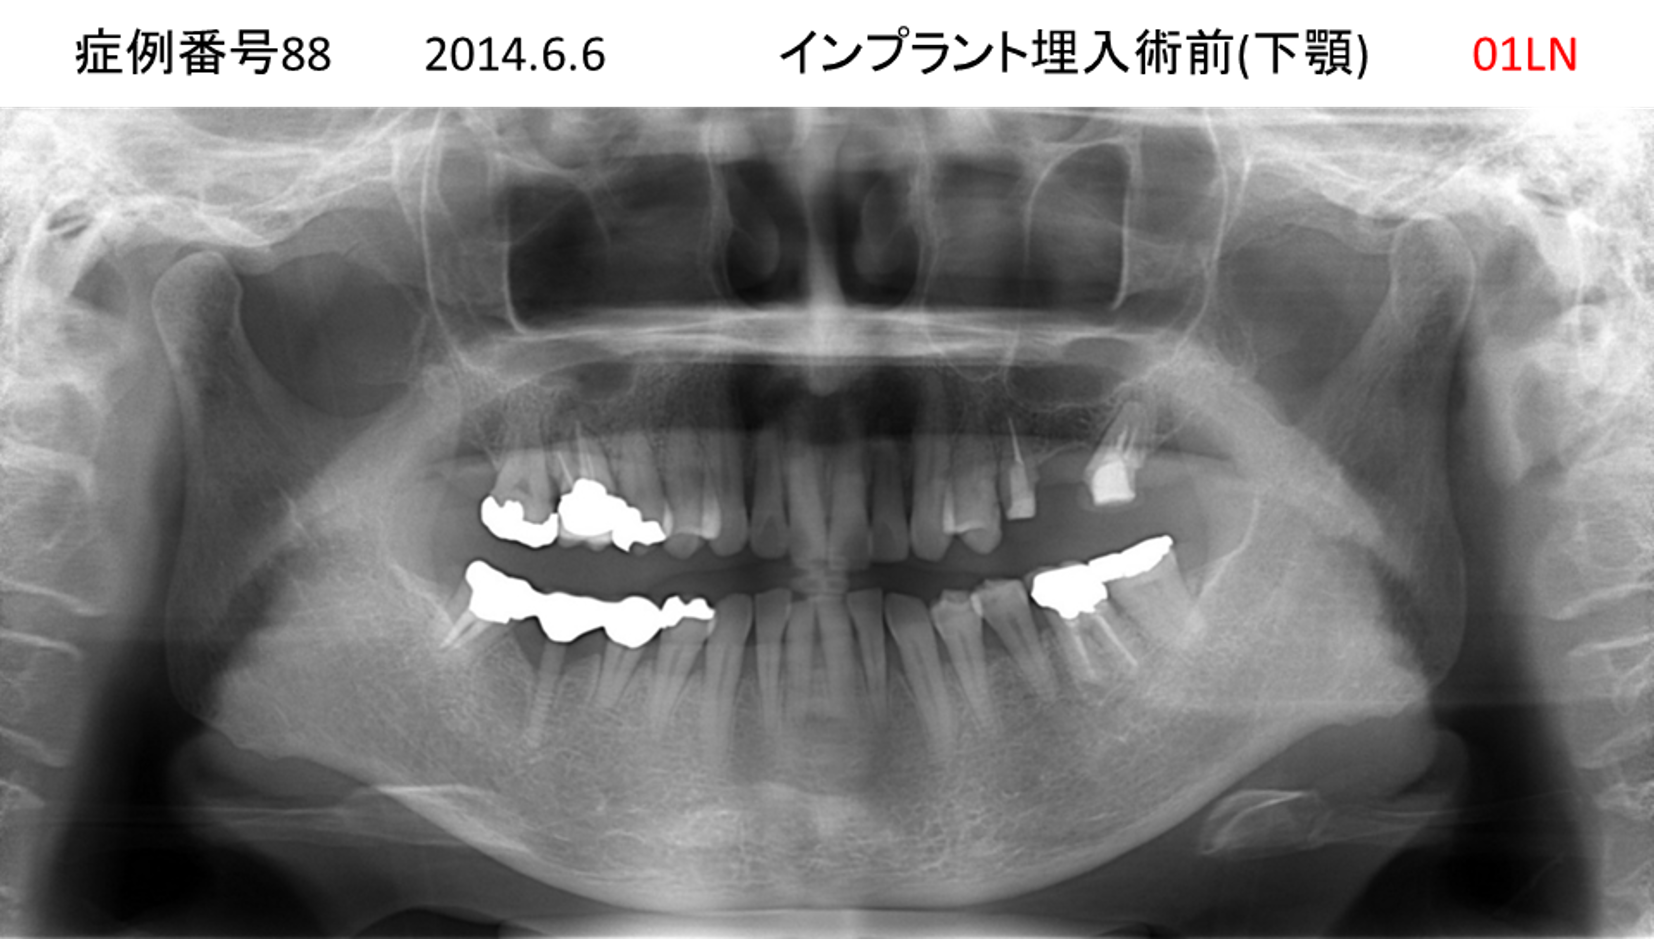

左下の奥歯が痛い患者様のインプラント症例

| 治療名称 |

インプラント |

| 治療費用 |

215万円+税 |

| 治療期間 |

5か月 |

| 患者さんの症状(主訴) |

左下の奥歯が痛い。 |

| 治療内容 |

| 治療結果 |

痛み無く、噛める。 |

| 治療の注意点(リスク/副作用) |

インプラントが壊れたら再治療が必要 |